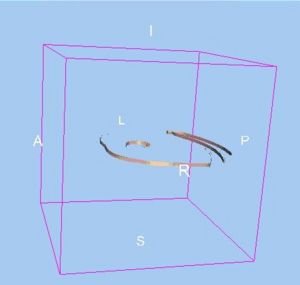

Background/Purpose: Related also to efforts within the Center for the Development of a Virtual Tumor, CViT (http://www.cvit.org), our research here (http://biosystems.mit.edu) focuses on developing multi-scale and multi-resolution (brain) cancer models. Using a hybrid 3D agent-based modeling platform we connect gene-protein interaction maps on the molecular and single cell level (Figure 1, left) up to the volumetric tumor scale of clinical MR-images. For the latter, we plan on using Slicer for segmentation of tumor-affected areas and 3D reconstruction of tumor volume and surface. Amongst the more challenging steps is the translation of these 2D in vivo imaging data onto our in silico lattices. Figure 1 (right) depicts a first step towards this approach where the yellow points depict the 3D surface reconstruction of a T1+Gd MRI while the blue and red points represent virtual tumor cells in attempt to match the real data points.